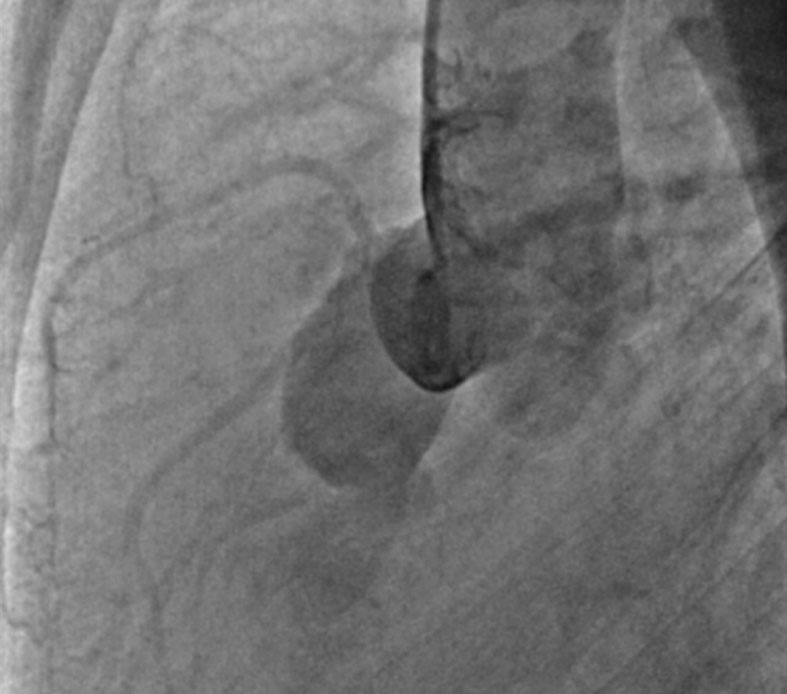

A 26-year-old male patient presented with dry cough, orthopnea, and PND & right-sided heart failure symptoms for 2 weeks. On examination, he has continuous murmur.

2D Echo shows fluid-filled cystic lesion with turbulent flow from aorta & LVEF 33 %

Cardiac MRI & aortic angiogram confirms diagnosis.